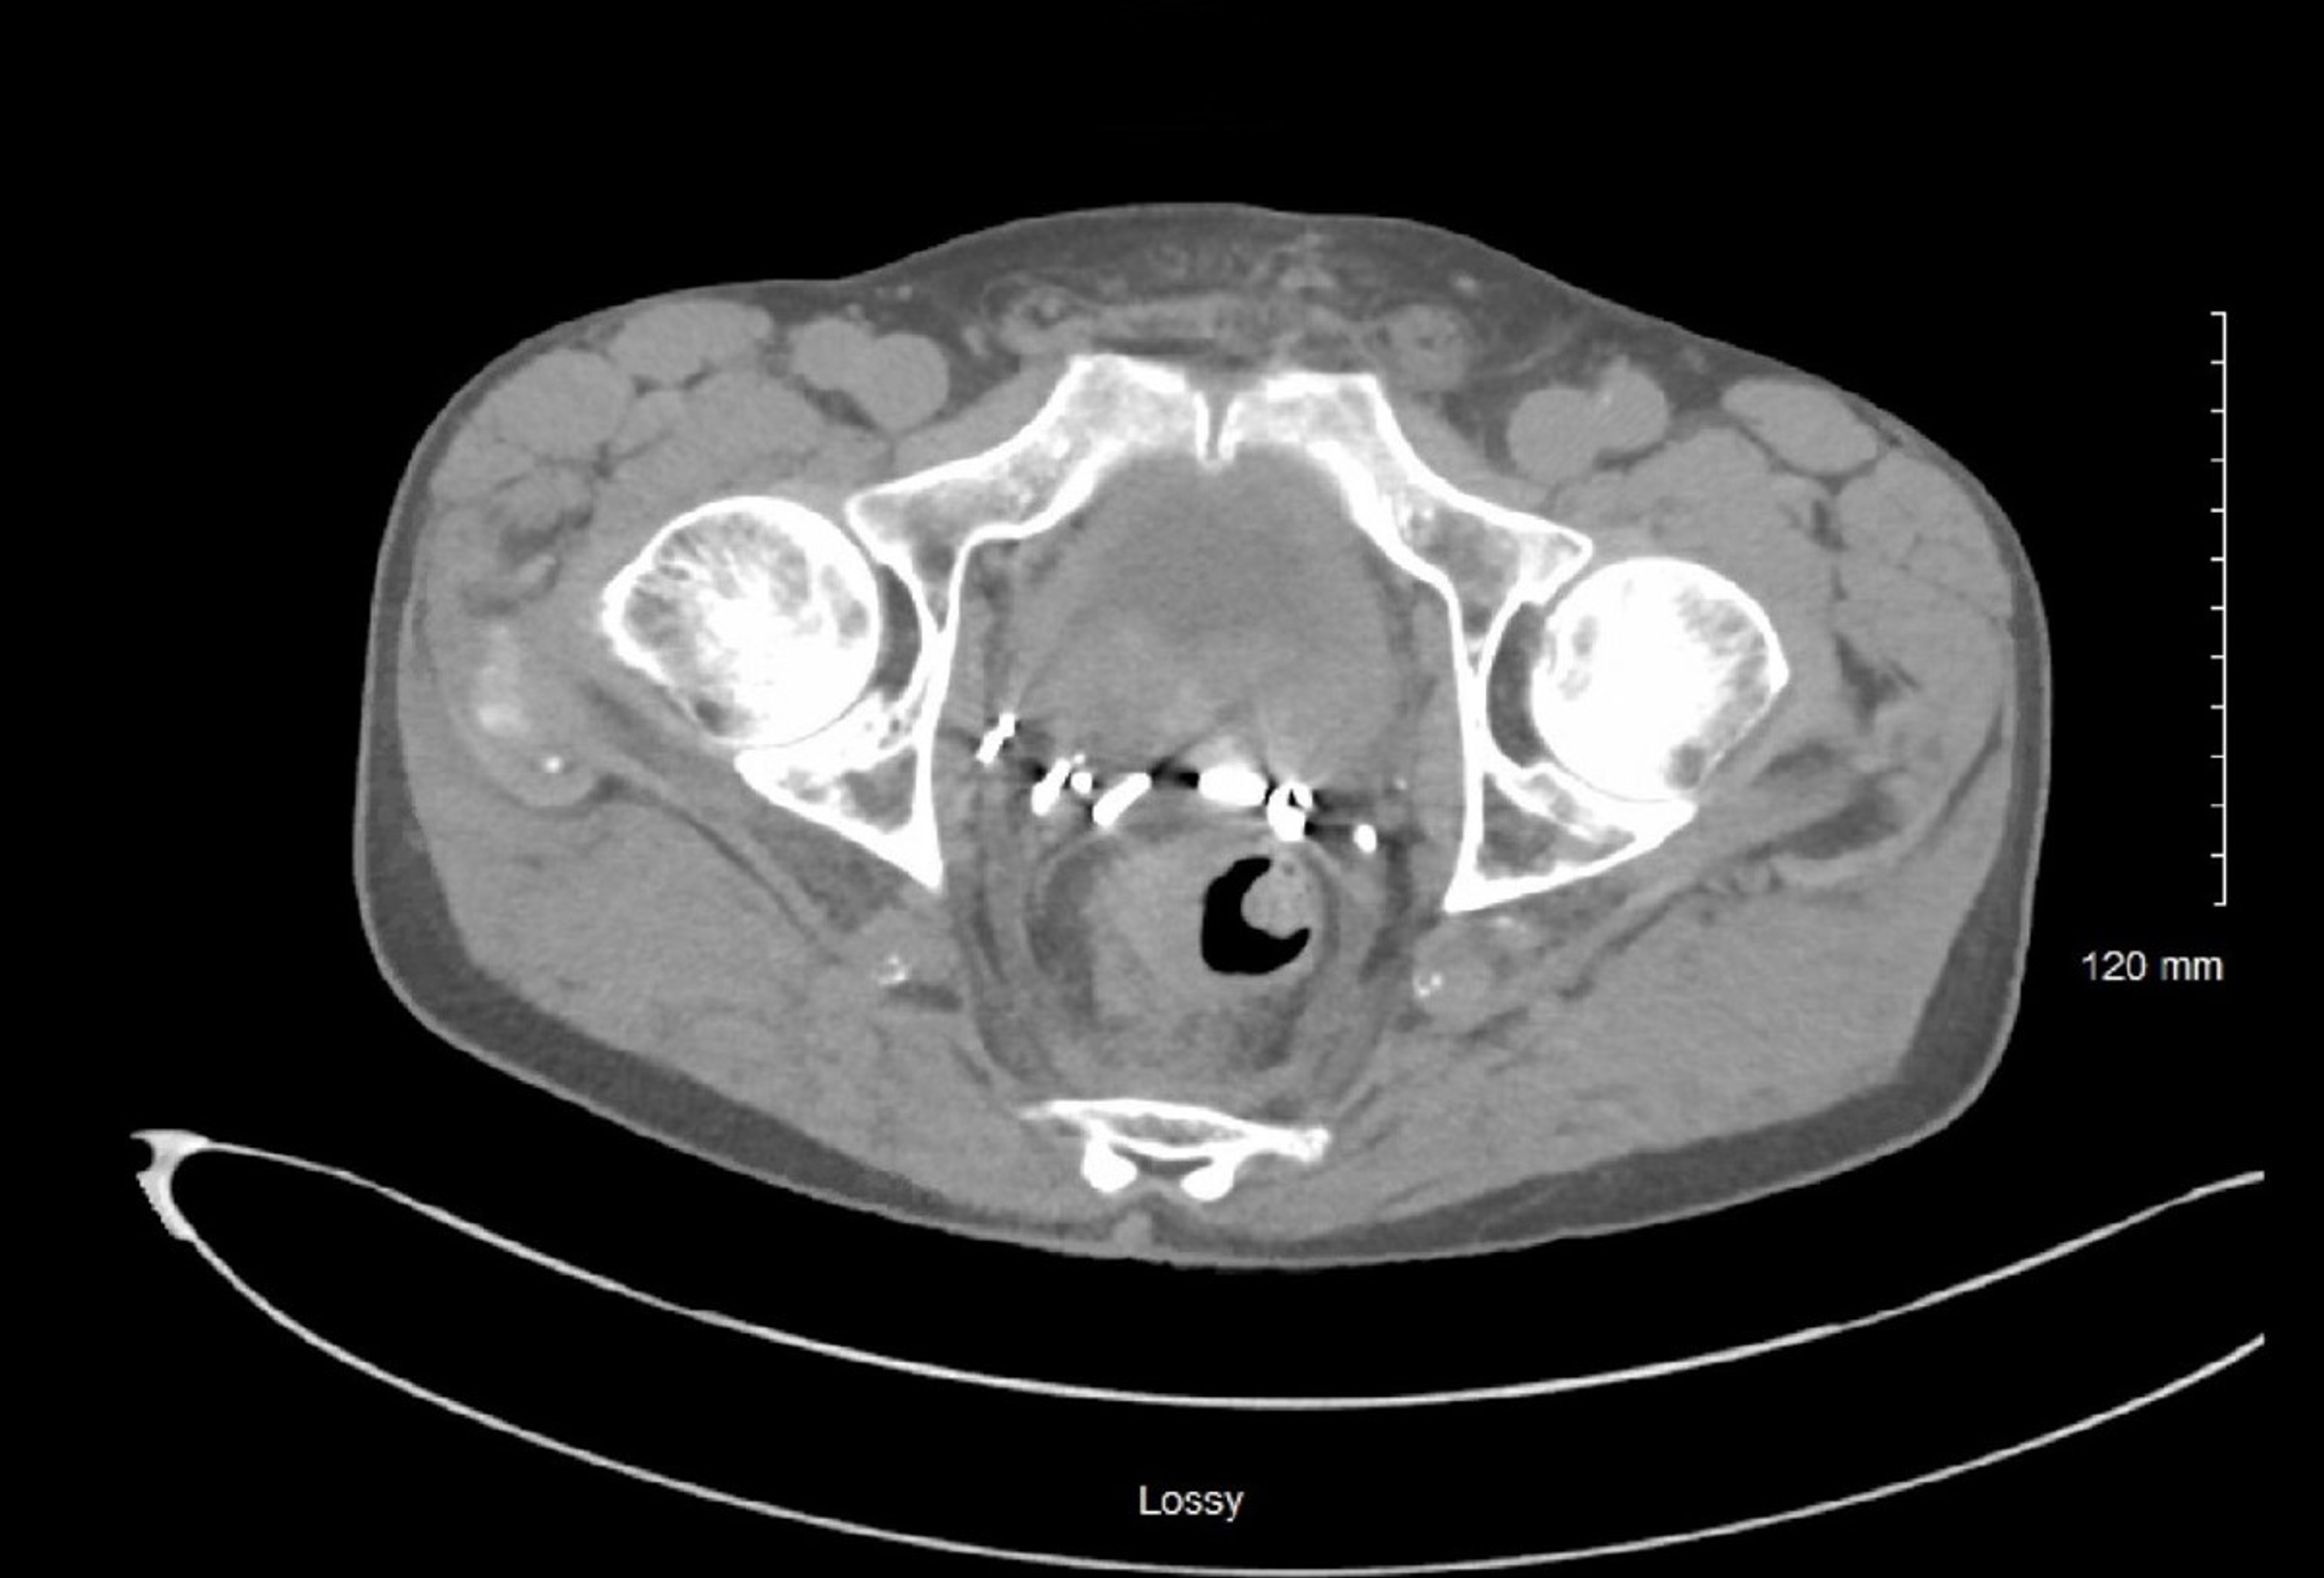

CT scan shows thickening of rectal wall with polypoid areas protruding What Does Rectal Wall Thickening Mean Introduction bowel wall thickening (bwt) is an increasing recognised entity seen on ct. Rectal thickening on ct means that the wall of the rectum is thicker than usual. This is a subjective findings for which the radiologist uses. Typical imaging findings include marked circumferential diffuse colonic wall. ≥3 mm for the colon and ≥5 mm for the rectum were considered. What Does Rectal Wall Thickening Mean.